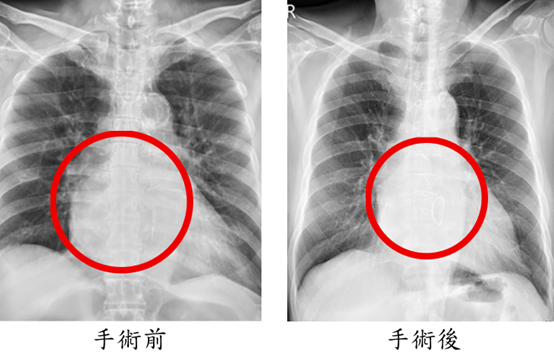

手術歷時8小時,依序完成冠狀動脈繞道手術、僧帽瓣修補、心室重建與冷凍去顫治療。術後隔天即順利移除呼吸器,再一天轉出加護病房,接受心臟復健後平安出院。術後一個月追蹤顯示,心臟收縮功能由原本32%提升至53%,瓣膜逆流消失,24小時心電圖亦未再出現心室性心律不整。陳先生恢復日常生活,並表示身體狀況比手術前更好;陳太太回憶從機上驚魂到返台治療的過程,對醫療團隊的專業與細心深表感謝與安心。

圖二、手術後三個月追蹤(右圖),X光顯示心臟明顯縮小,心室收縮功能從術前33%進步到53%,24小時心電圖監控沒有發生心室性心律不整。